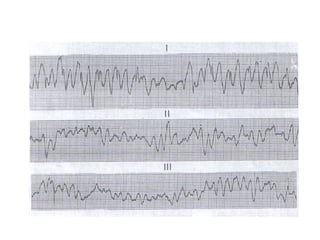

FIBRILLATION VENTRICULAIRE

Caractères ECG

Activité ventriculaire rapide, irrégulière

réalisant des oscillations sans retour à la

ligne isoélectrique.

C’est le trouble du rythme le plus grave

correspondant à l’arrêt cardio-circulatoire

CAT: massage cardiaque et choc électrique

(voir réanimation cardio-pulmonaire)